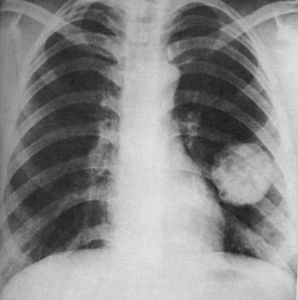

X線胸片、體層攝影、支氣管造影、CT掃描等檢查對於顯示和分析肺部良性腫瘤的特徵具有較高的診斷價值,最後確切診斷依靠病理組織學檢查。治療